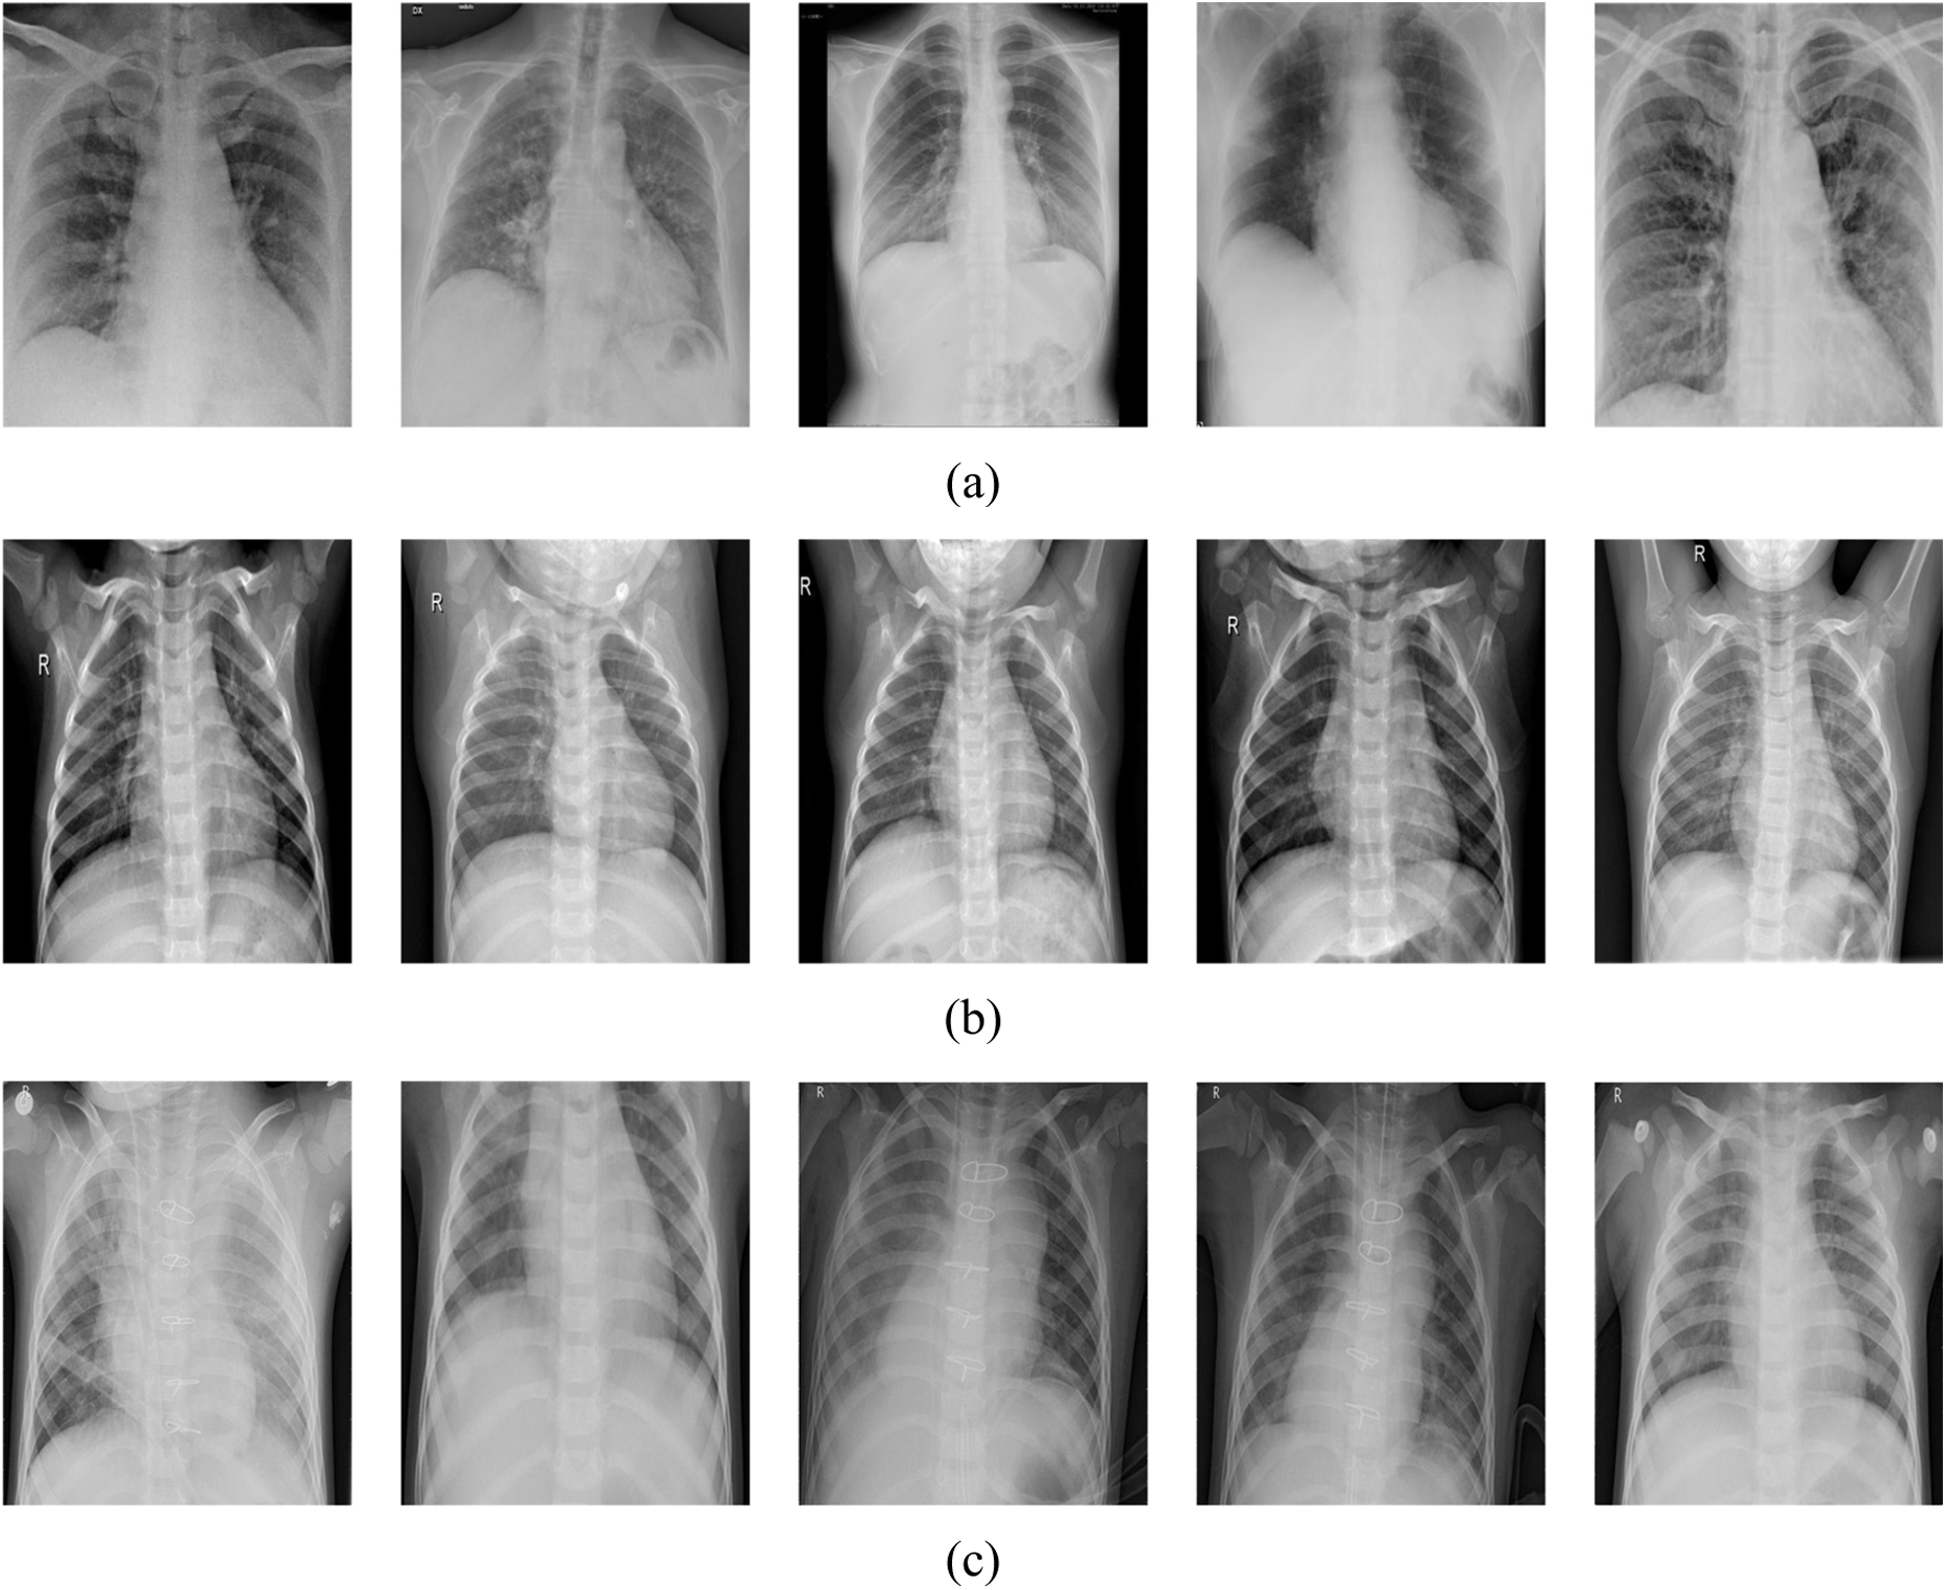

The authors included two open-source datasets in their study. Chest X-ray images for COVID-19 positive cases were taken from the GitHub repository, prepared by the authors in [44,45]. Samples of the used dataset in this study are shown in Fig. 6.

Figure 6: Samples of the used dataset in this project, (a) positive COVID-19, (b) normal, (c) pneumonia

In this research, three classes of images were used. X-ray images of positive COVID-19, ARDS, SARS, Streptococcus, Pneumocystis, and other pneumonia types were employed. The first dataset contains only 180 images for 118 COVID-19 cases and the remaining 42 images for 25 cases of pneumocystis, Streptococcus, and SARS were identified as pneumonia. The second dataset includes 6012 pneumonia cases and 8851 normal cases. As stated, only 180 positive COVID-19 instances are available, which are little data for one class in comparison to other classes. Mixing large numbers of normal and pneumonia images with only few COVID-19 images for training leads to identifying pneumonia and normal cases more effectively by the network than COVID-19 cases due to unbalanced dataset.